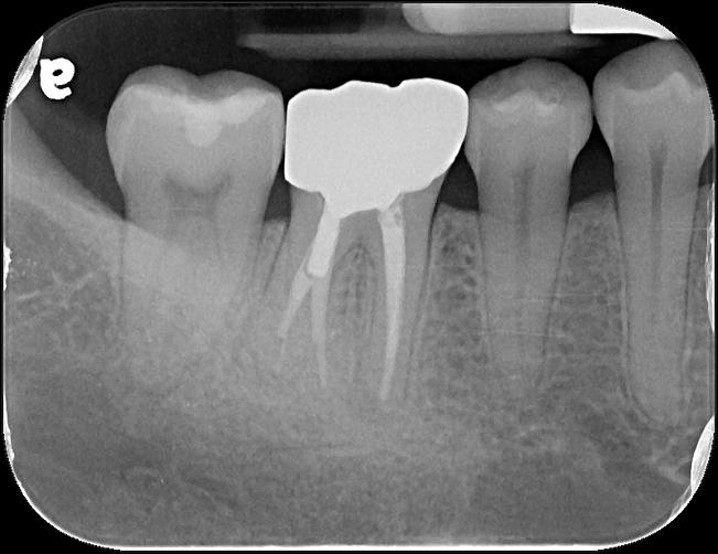

治療前,右下第一大臼齒腫脹

治療前,根管已治療過